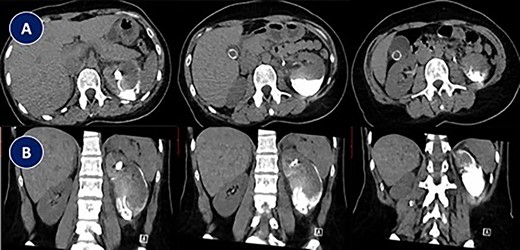

This is a 33-year-old female with no co-morbid conditions, presented to another center with severe left flank pain for 3 days associated with nausea and vomiting. She had abdominal non-contrast CT showing 3-mm left distal ureteric stone. Patient was treated with medical expulsive therapy, which did not work for 14 days, and patient came to ER twice during that period. Therefore, patient underwent left ureteroscopy, during the procedure stone was removed, decision was to insert a DJ stent. According to the urologist, DJ stent was misplaced completely proximally. Therefore, he inserted another DJ stent. Patient was in severe pain postoperatively; abdominal CT scan that was carried out showed complete misplacement of DJ stent into subcapsular renal space [Fig. 1]. After 1 week, patient was referred to our center and admitted due to persistent left flank pain associated with intermittent gross hematuria. Physical examination was unremarkable apart from left flank tenderness. Her blood investigations showed: WBC: 7.87 × 109/L, RBC: 3.86 × 109/L, Hgb: 10.4 g/dl and creatinine 50 μmol/L. Urine analysis showed: RBC: 56, WBC: 79 and nitrate was negative. Urine culture showed negative growth for organisms. Abdominal non-contrast CT was performed in our center; images were discussed with senior radiologist who could not confirm if the tip of misplaced subcapsular renal DJ stent was in the left upper calyx; however, he confirmed adequately positioned second left DJ stent.

Abdominal CT scan showing complete misplacement of DJ stent into subcapsular renal space. (A) CT scan image (Axial). (B) CT scan image (Coronal).